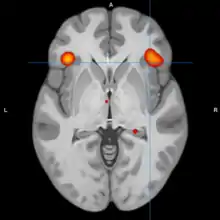

A model of functional neuroanatomy produced by a workgroup led by Stephen M. Strakowski concluded that bipolar was characterized by reduced connectivity, due to abnormal pruning or development, in the prefrontal-striatal-pallidal-thalamic-limbic network leading to dysregulated emotional responses. This model was supported by a number of common neuroimaging findings. Dysregulation of limbic structures is evinced by the fact that hyperactivity in the amygdala in response to facial stimuli has been consistently reported in mania.[33] While amygdala hyperactivity is not a uniform finding, a number of methodological challenges could explain discrepancies. As most studies utilize fMRI to measure blood-oxygen-level dependent signal, excess baseline activity could result in null findings due to subtraction analysis. Furthermore, heterogenous study design could mask consistent hyperactivity to specific stimuli. Regardless of directionality of amygdala abnormalities, as the amygdala plays a central role in emotional systems, these findings support dysfunctional emotional circuits in bipolar. A general reduction in ventrolateral prefrontal cortex activity is observed in bipolar, and is lateralized with regard to mood (i.e., left-depression, right-mania), and may underlie amygdala abnormalities. The dorsal ACC is commonly under-activated in bipolar, and is generally implicated in cognitive functions, while the ventral ACC is hyperactive and implicated in emotional functions. Combined, these abnormalities support the prefrontal-striatal-pallidial-thalamic limbic network underlying dysfunction in emotional regulation in bipolar disorder.[34] Strakowski, along with DelBello and Adler have put forward a model of "anterior limbic" dysfunction in bipolar disorder in a number of papers.[35][36][37][38][39]

Studies examining resting blood flow, or metabolism generally observed abnormalities dependent upon mood state. Bipolar depression is generally associated with dlPFC and medial orbitofrontal cortex hypometabolism. Less consistent associations include reduced temporal cortex metabolism, increased limbic metabolism and reduced ACC metabolism. Mania is also associated with dlPFC and OFC hypometabolism. Limbic hypermetabolism is more consistent than in bipolar depression, but the overall study quality is low due to limitations associated with neuroimaging in acutely manic patients.[70] Another review reported that mania is generally associated with frontal/ventral hypoactivation, while depression is generally associated with the opposite. A degree of lateralization with regard to abnormalities has been reported, with mania being associated with the right hemisphere, and depression the left. Trait abnormalities in euthymic patients have been observed, including hypoactivity in the ventral prefrontal cortex, and hyperactivity in the amygdala.[71]

During cognitive or emotional tasks, functional neuroimaging studies, consistently find hyperactivation of the basal ganglia, amygdala, and thalamus. Prefrontal abnormalities are less consistently reported, although hyperactivation in the ventral prefrontal cortex is a fairly consistent finding.[72] Hyperactivity in the amygdala and hypoactivity in the medial and ventral prefrontal cortex during exposure to emotional stimuli has been interpreted as reflecting dysfunction in emotional regulation circuits. Increased effective connectivity between the amygdala and orbitofrontal cortex, and elevated striatal responsiveness during reward tasks have been interpreted as hyper-responsiveness in positive emotion and reward circuitry. The abnormal activity in these circuits has been observed in non-emotional tasks, and is congruent with changes in grey and white matter in these circuits.[73] Neural response during reward tasks differentiates unipolar depression from bipolar depression, with the former being associated with reduced neural response and the latter being associated with elevated neural response.[74] An ALE meta analysis of functional neuroimaging comparing adults and adolescents found a larger degree of hyperactivity in the inferior frontal gyrus and precuneus, as well as a larger degree of hypoactivity in the anterior cingulate cortex in adolescents relative to adults[75]

A meta analysis using region of interest (as opposed to statistical parametric mapping) analysis reported abnormalities across paradigms for euthymic, depressed, and manic subjects. In bipolar mania, reduced activity was reported in the superior, middle, and inferior frontal gyri, while increased activity was reported in the parahippocampal, superior temporal, middle temporal, and inferior temporal gyri. In bipolar depression, reduced activity was reported in the sgACC, ACC, and middle frontal gyrus. In euthymia, reduced activity was reported in the dlPFC, vlPFC, and ACC, while increased activity was reported in the amygdala. During studies examining response to emotional faces, both mania and euthymia were reported to be associated with elevated amygdala activity.[77]

An activation likelihood estimate meta analysis of bipolar studies that used paradigms involving facial emotions reported a number of increases and decreases in activation compared to healthy controls. Elevated activity was reported in the parahippocampal gyrus, putamen, and pulvinar nuclei, while reduced activity was reported bilaterally in the inferior frontal gyrus. Compared to major depressive disorder, bipolar patients overactivated the vACC, pulvinar nucleus, and parahippocampus gyrus/amygdala to a greater degree, while underactivating the dACC. Bipolar subjects overactivated parahippocampus for both fearful and happy expressions, while the caudate and putamen were overactive for happiness and fear respectively. Bipolar subjects also underactivated the ACC for both fearful and happy expressions, while the IFG was underactivated for fearful expressions only. These results were interpreted as reflecting increased engagement with emotionally salient stimuli in bipolar disorder.[78]